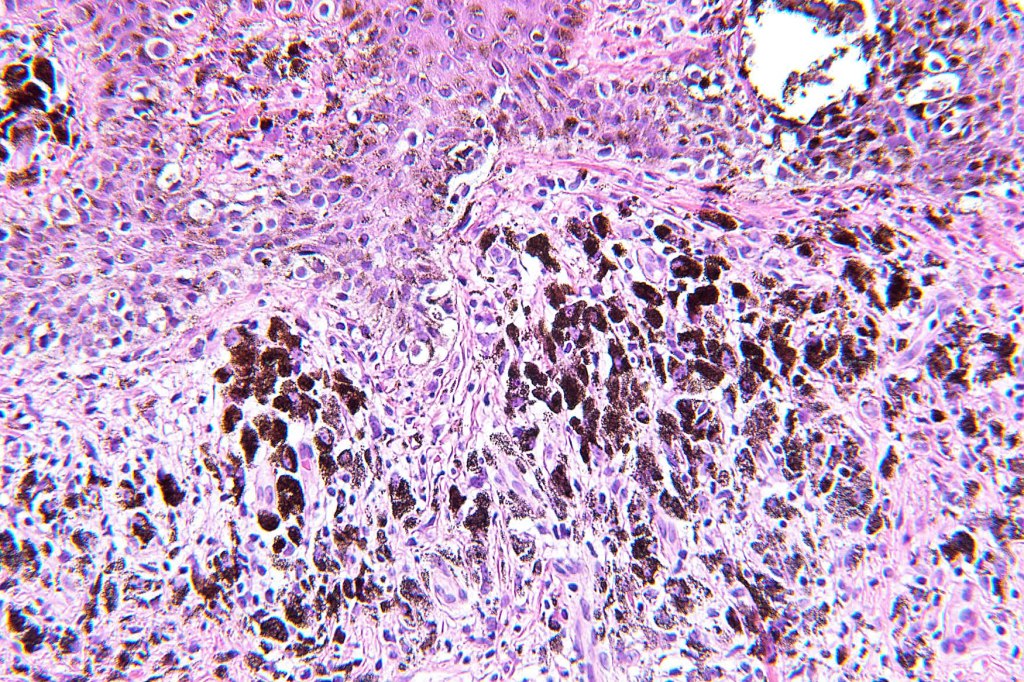

Histological features

•May affect the tumor in part or whole

•Enlarged cells with copious eosinophilic, foamy or clear cytoplasm (some authors include melanoma with clear cell change in the same category)

•Variable pigmentation

•DPAS granules

•Thought to be a result of abnormal or degenerative melanosome change